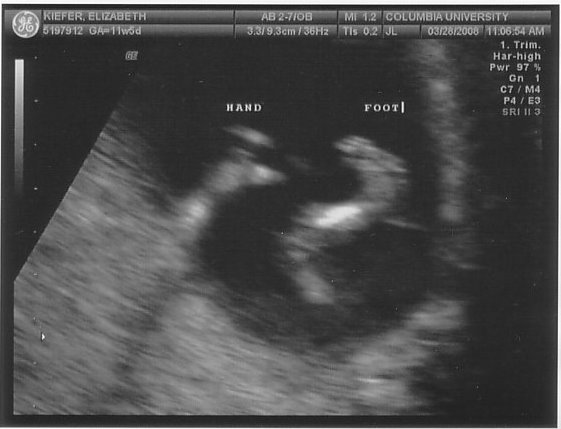

On Friday we headed uptown for our second ultrasound. Nobody told me that baby m0ves around in there at 12 weeks (thanks for the help, parenting books, keep up the good work!), so I just about freaked out when he arched his back and rubbed his face (or she/her, of course, we don’t find that out for another 6 weeks). Fortunately our tech was used to people gasping loudly. Sooooo cool.

In case you were wondering if I was going to be a stereotype of a dad, I’m including all 5 blurry blob pictures here. And if I had an hour long movie of same, I’d post that, too.